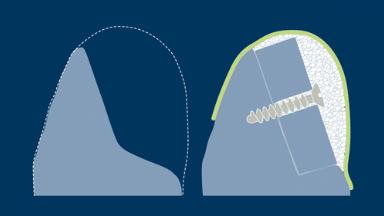

Biological Principles of Bone Grafting

A prerequisite for a successful implant treatment is that the implant is placed with primary stability and successfully integrates into the jaw bone in a prosthodontically driven, predetermined position. For osseointegration of the implant to take place, it is essential that the living bone be treated carefully during the procedure to place the implant. Clinicians therefore need to understand the composition and nature of living bone before undertaking dental implant procedures.

- describe basic aspects of bone biology

- classify bone grafts and substitutes

- describe key aspects of bone graft healing